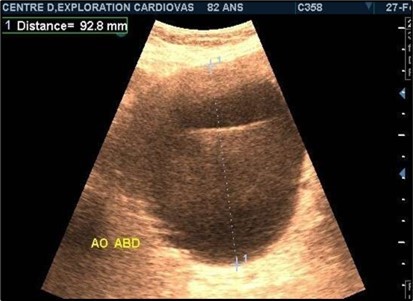

Aneurysms were thrombosed in 24 patients (75%). (Figure 3) and (Figure 4) Arterial occlusion was found in 11 patients (73.33%) and significant stenosis in 4 patients (36.36%). (Table 7).

Figure 3.Large fusiform subrenal abdominal aortic aneurysm of 9.28cm thrombosed at 4/5 in an 82-year-old woman (CEC ‘Saint-Esprit’ from AMP-MCV).

Figure 4.Large fusiform subrenal abdominal aortic aneurysm of 9.28cm thrombosed at 4/5 in an 82-year-old woman (CEC ‘Saint-Esprit’ from AMP-MCV).

The aneurysms had extensions to other arteries in 21 patients (65.63%) distributed as follows: superior mesenteric artery (11.76%) (Figure 3) and (Figure 4), celiac trunk (14.23%), iliac arteries (57.14%) femoral arteries (19.05%). (Figure 5) and (Figure 6)